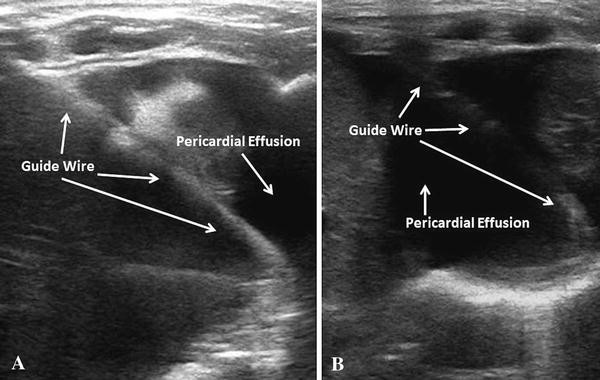

Step 5 – Guidewire Confirmation

Advance 20–30 cm or until resistance.

The wire should coil around the heart.

Confirm in multiple views before dilation.

Failure to confirm risks dilating into a cardiac chamber — life-threatening.